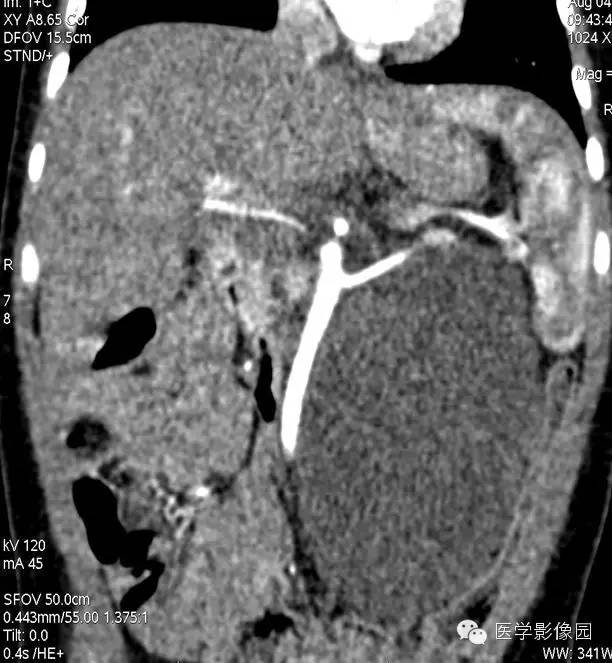

5——增强冠状位重建

6——增强冠状位重建